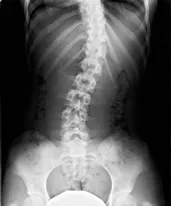

左右どちらかの腸骨が上がっている、または下がっている上体です。どちらかの骨の位置が上下することで左右のバランスが崩れることで、背骨そのものが大きく歪んでしまうことで、左右の足の長さが違う、肩の高さが違ってしまうことになります。

当院独自の検査

モアレトポグラフィ

カラダのゆがみがあると、自律神経のバランスを崩して自然治癒力が低下することが多いです。カラダのゆがみを視覚的に確認する検査です。